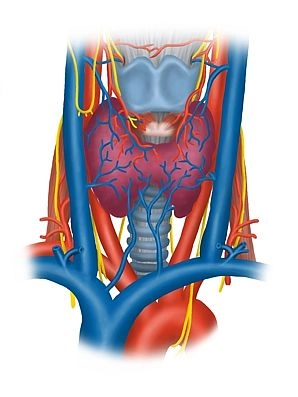

Vasos Sanguíneos

A artéria carótida comum se divide na borda superior da cartilagem tireoide no nível do seu seio carotídeo (receptores para pressão arterial e quimiorreceptores para gases sanguíneos) em seus ramos interno e externo e corre previamente imediatamente lateral na bainha carotídea ao lado da traqueia e esôfago cranialmente. Aqui ela toca como um grande vaso os lobos tireoidianos direito e esquerdo. A veia jugular interna surge do seio sigmoide do crânio, coletando sangue do crânio e pescoço, inicialmente alinhando-se com a artéria carótida interna na bainha carotídea, depois correndo mais lateralmente e circundando a artéria carótida comum e o nervo vago (N. X) lateralmente.

Nervos

Além do nervo vago e seu ramo superior para a laringe (nervo laríngeo superior → músculo cricotireóideo anterior, bem como mucosa da metade superior da laringe), a ansa cervical profunda (raízes superior e inferior, de C1-C3) desce lateralmente na área da glândula tireoide para inervar os três músculos mencionados do triângulo anterior do pescoço e o nervo cervical transverso (de C2/3, inervação cutânea, platisma).